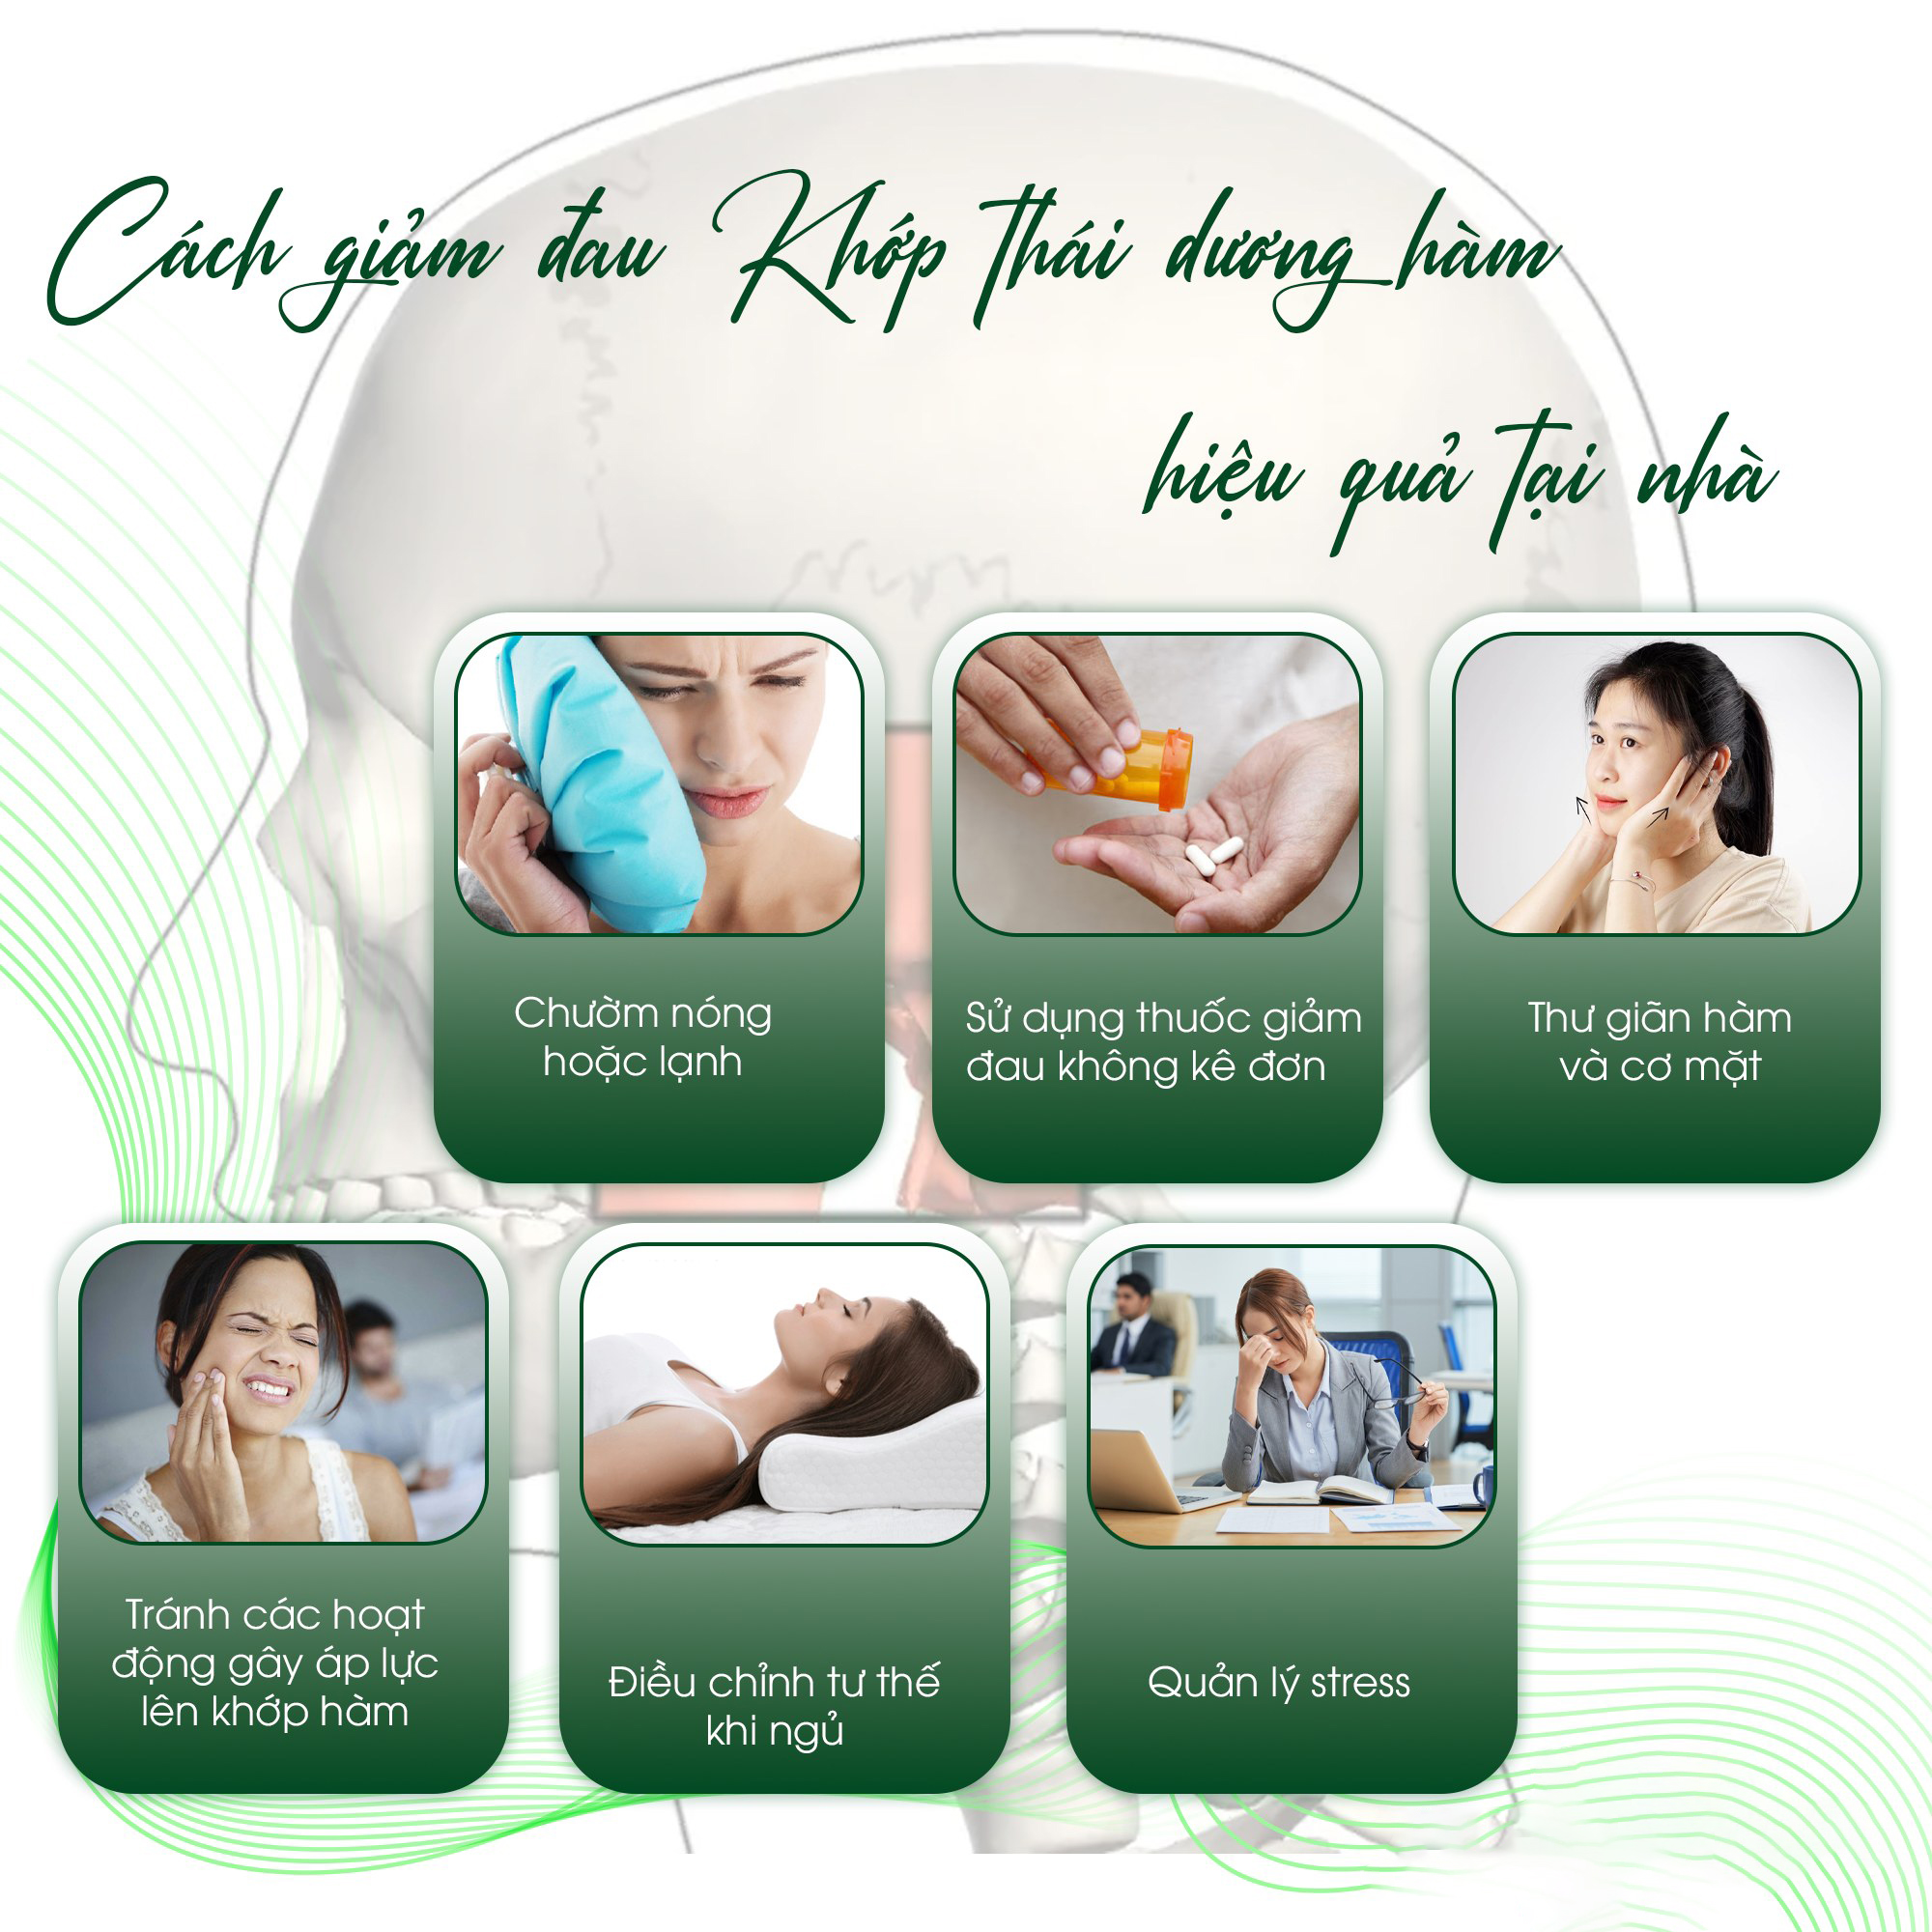

Làm gì để giảm đau và ngăn ngừa rối loạn chức năng khớp thái dương hàm (TMD)?

CÁCH GIẢM ĐAU HIỆU QUẢ TẠI NHÀ ngăn ngừa rối loạn chức năng khớp Thái Dương Hàm (TMD) - Chườm nóng hoặc lạnh Chườm lạnh: Giúp giảm viêm, giảm đau nhanh. Đặt túi đá bọc trong khăn lên vùng thái dương và khớp hàm trong 15-20 phút. Chườm nóng: Thư giãn cơ hàm, giảm căng thẳng. Dùng khăn ấm hoặc túi chườm nóng đặt lên khớp 15-20 phút. Luân phiên nóng – lạnh: Một số người thấy hiệu quả khi thay đổi giữa hai phương pháp này. - Sử dụng thuốc giảm đau không kê đơn: Ibuprofen hoặc naproxen có thể giúp giảm viêm và đau. Sử dụng theo hướng dẫn của dược sĩ. - Thư giãn hàm và cơ mặt Thực hiện các bài tập nhẹ nhàng như mở – đóng miệng có kiểm soát, massage cơ hàm, vuốt lưỡi lên vòm miệng. Tránh nghiến răng, siết chặt hàm khi căng thẳng. - Tránh các hoạt động gây áp lực lên khớp hàm Hạn chế nhai kẹo cao su, ăn thức ăn cứng hoặc quá dai. Cắt nhỏ thức ăn để giảm áp lực lên cơ hàm. Tránh há miệng quá to khi ngáp, hát hoặc cắn đồ cứng. - Điều chỉnh tư thế khi ngủ Ngủ nằm ngửa giúp tránh áp lực lên hàm. Nếu nằm nghiêng, hãy dùng gối hỗ trợ cổ hợp lý. - Quản lý stress Căng thẳng có thể làm bạn nghiến răng, siết chặt hàm. Thực hành thiền, yoga, hít thở sâu để thư giãn.